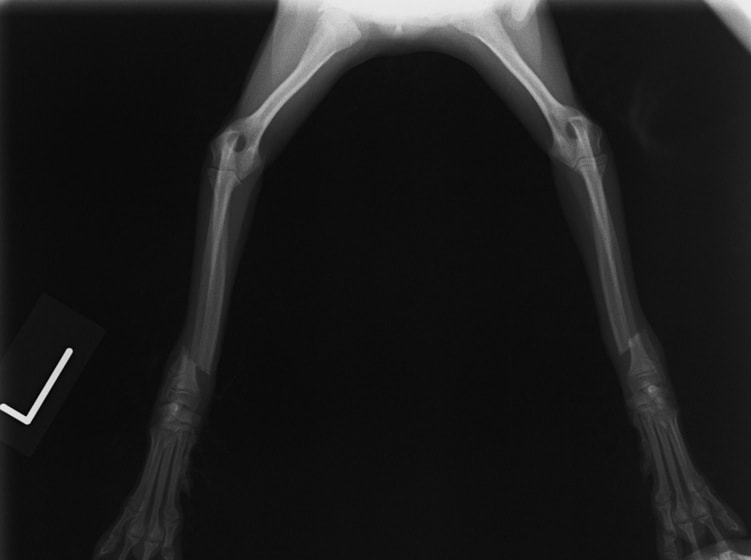

ペルシャ猫 11ヶ月齢 雄

他院にて左大腿骨遠位の成長板骨折(salter-harrisⅠ型)が認められており、治療相談を目的として来院。当院にて、キルシュナーワイヤーを用いたピンニングにより骨折部位の整復を行いました。術後の経過は良好で、現在も経過観察中です。

術前レントゲン

術後レントゲン